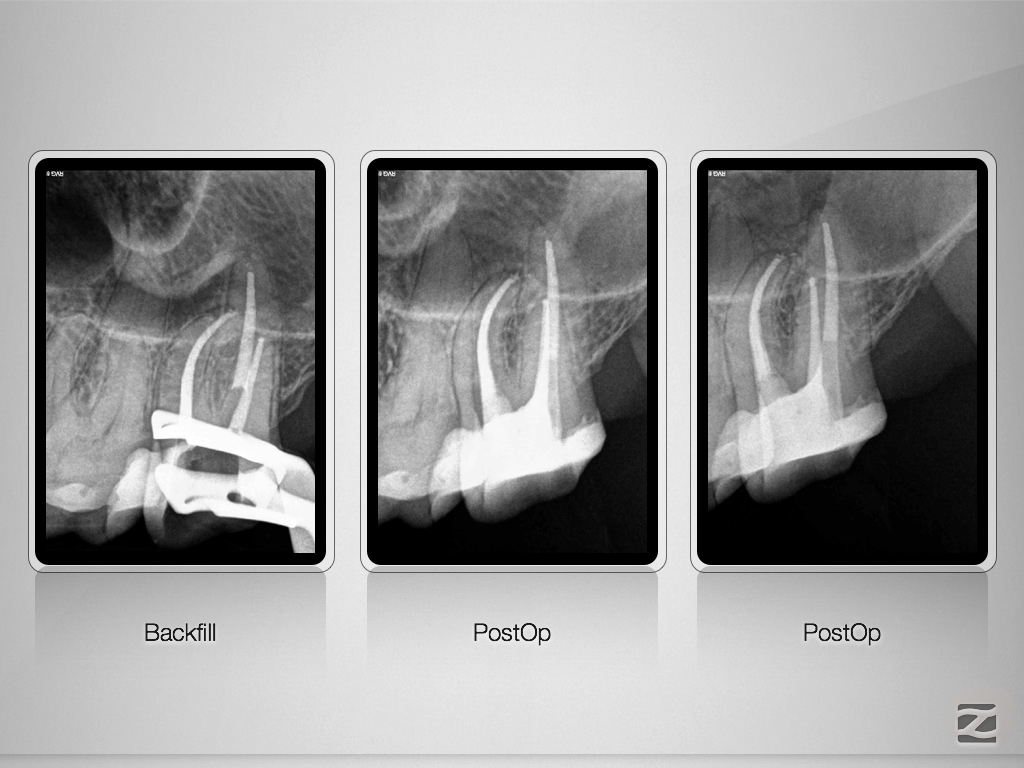

27D.008

Die gute alte Hedströmfeile